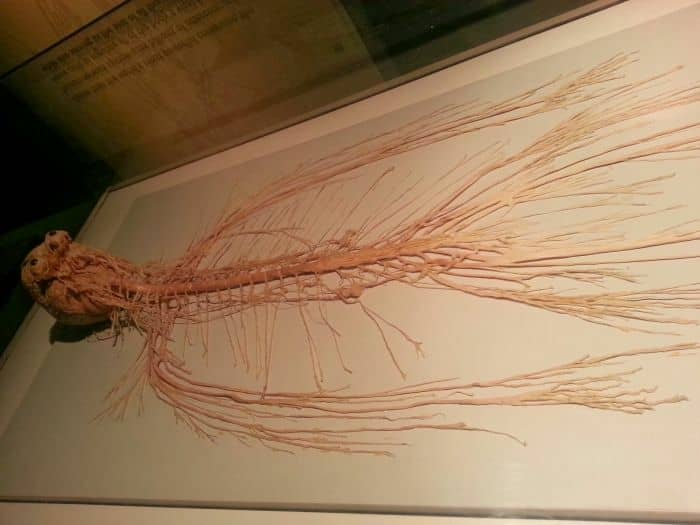

Your nerves are as thin as strings. First time I opened up a body and studied all the anatomy, it was shocking how nerves and blood vessels were incredibly thin. Like we get hit by balls or fall on rocks or do martial arts and dont think much of it but the wiring of your entire body is so thin it’s sobering to realize how fragile we really are.

The spinal cord itself looks and feels like crab meat when it’s pulled out of the vertebrae.